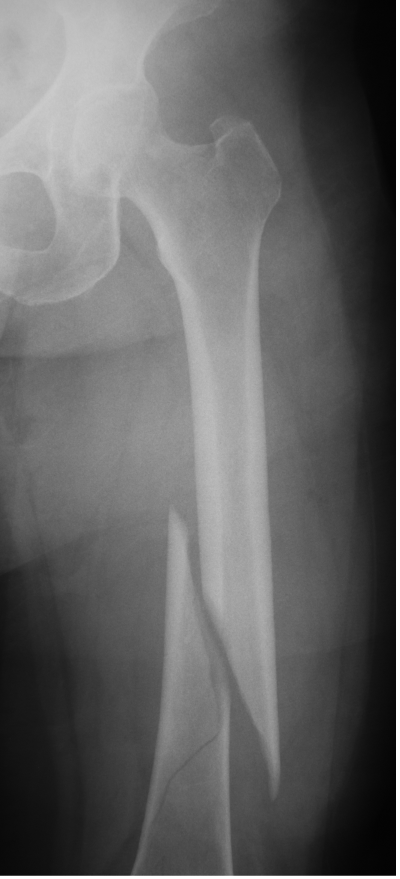

Femur fracture

age 13

Tibial fracture

age 57